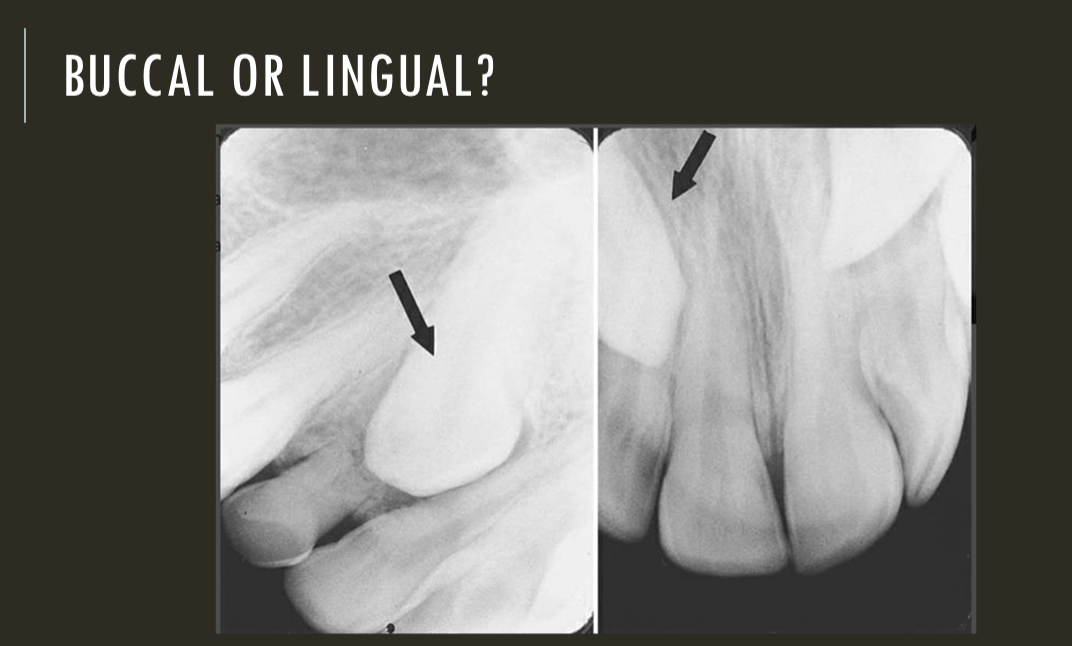

buccal object rule

expose 1st image (PA or bw)

take a second image with a different H or V angulation aka same area different angle

compare images to see how the object shifted in the image

SLOB

lingual

right angle technique

buccal

lingual

lingual

buccal

unable to assess from this single image the objects buccal-lingual position relative to the teeth